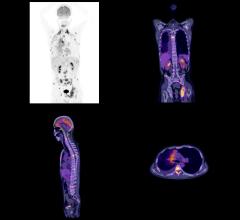

A new study involving patients with stage IV cancer finds treatment with radiation therapy and immunotherapy can halt the growth of tumors by stimulating the body’s immune system to attack the cancer. In the phase II trial, patients with end-stage cancer that had spread to the lungs or liver demonstrated a favorable response to the combined treatment. Between 30 and 60 percent of the patients, depending on the treatment arm, found that their cancer stopped spreading. Findings were presented at the 59th Annual Meeting of the American Society for Radiation Oncology (ASTRO), Sept. 24-27 in San Diego.